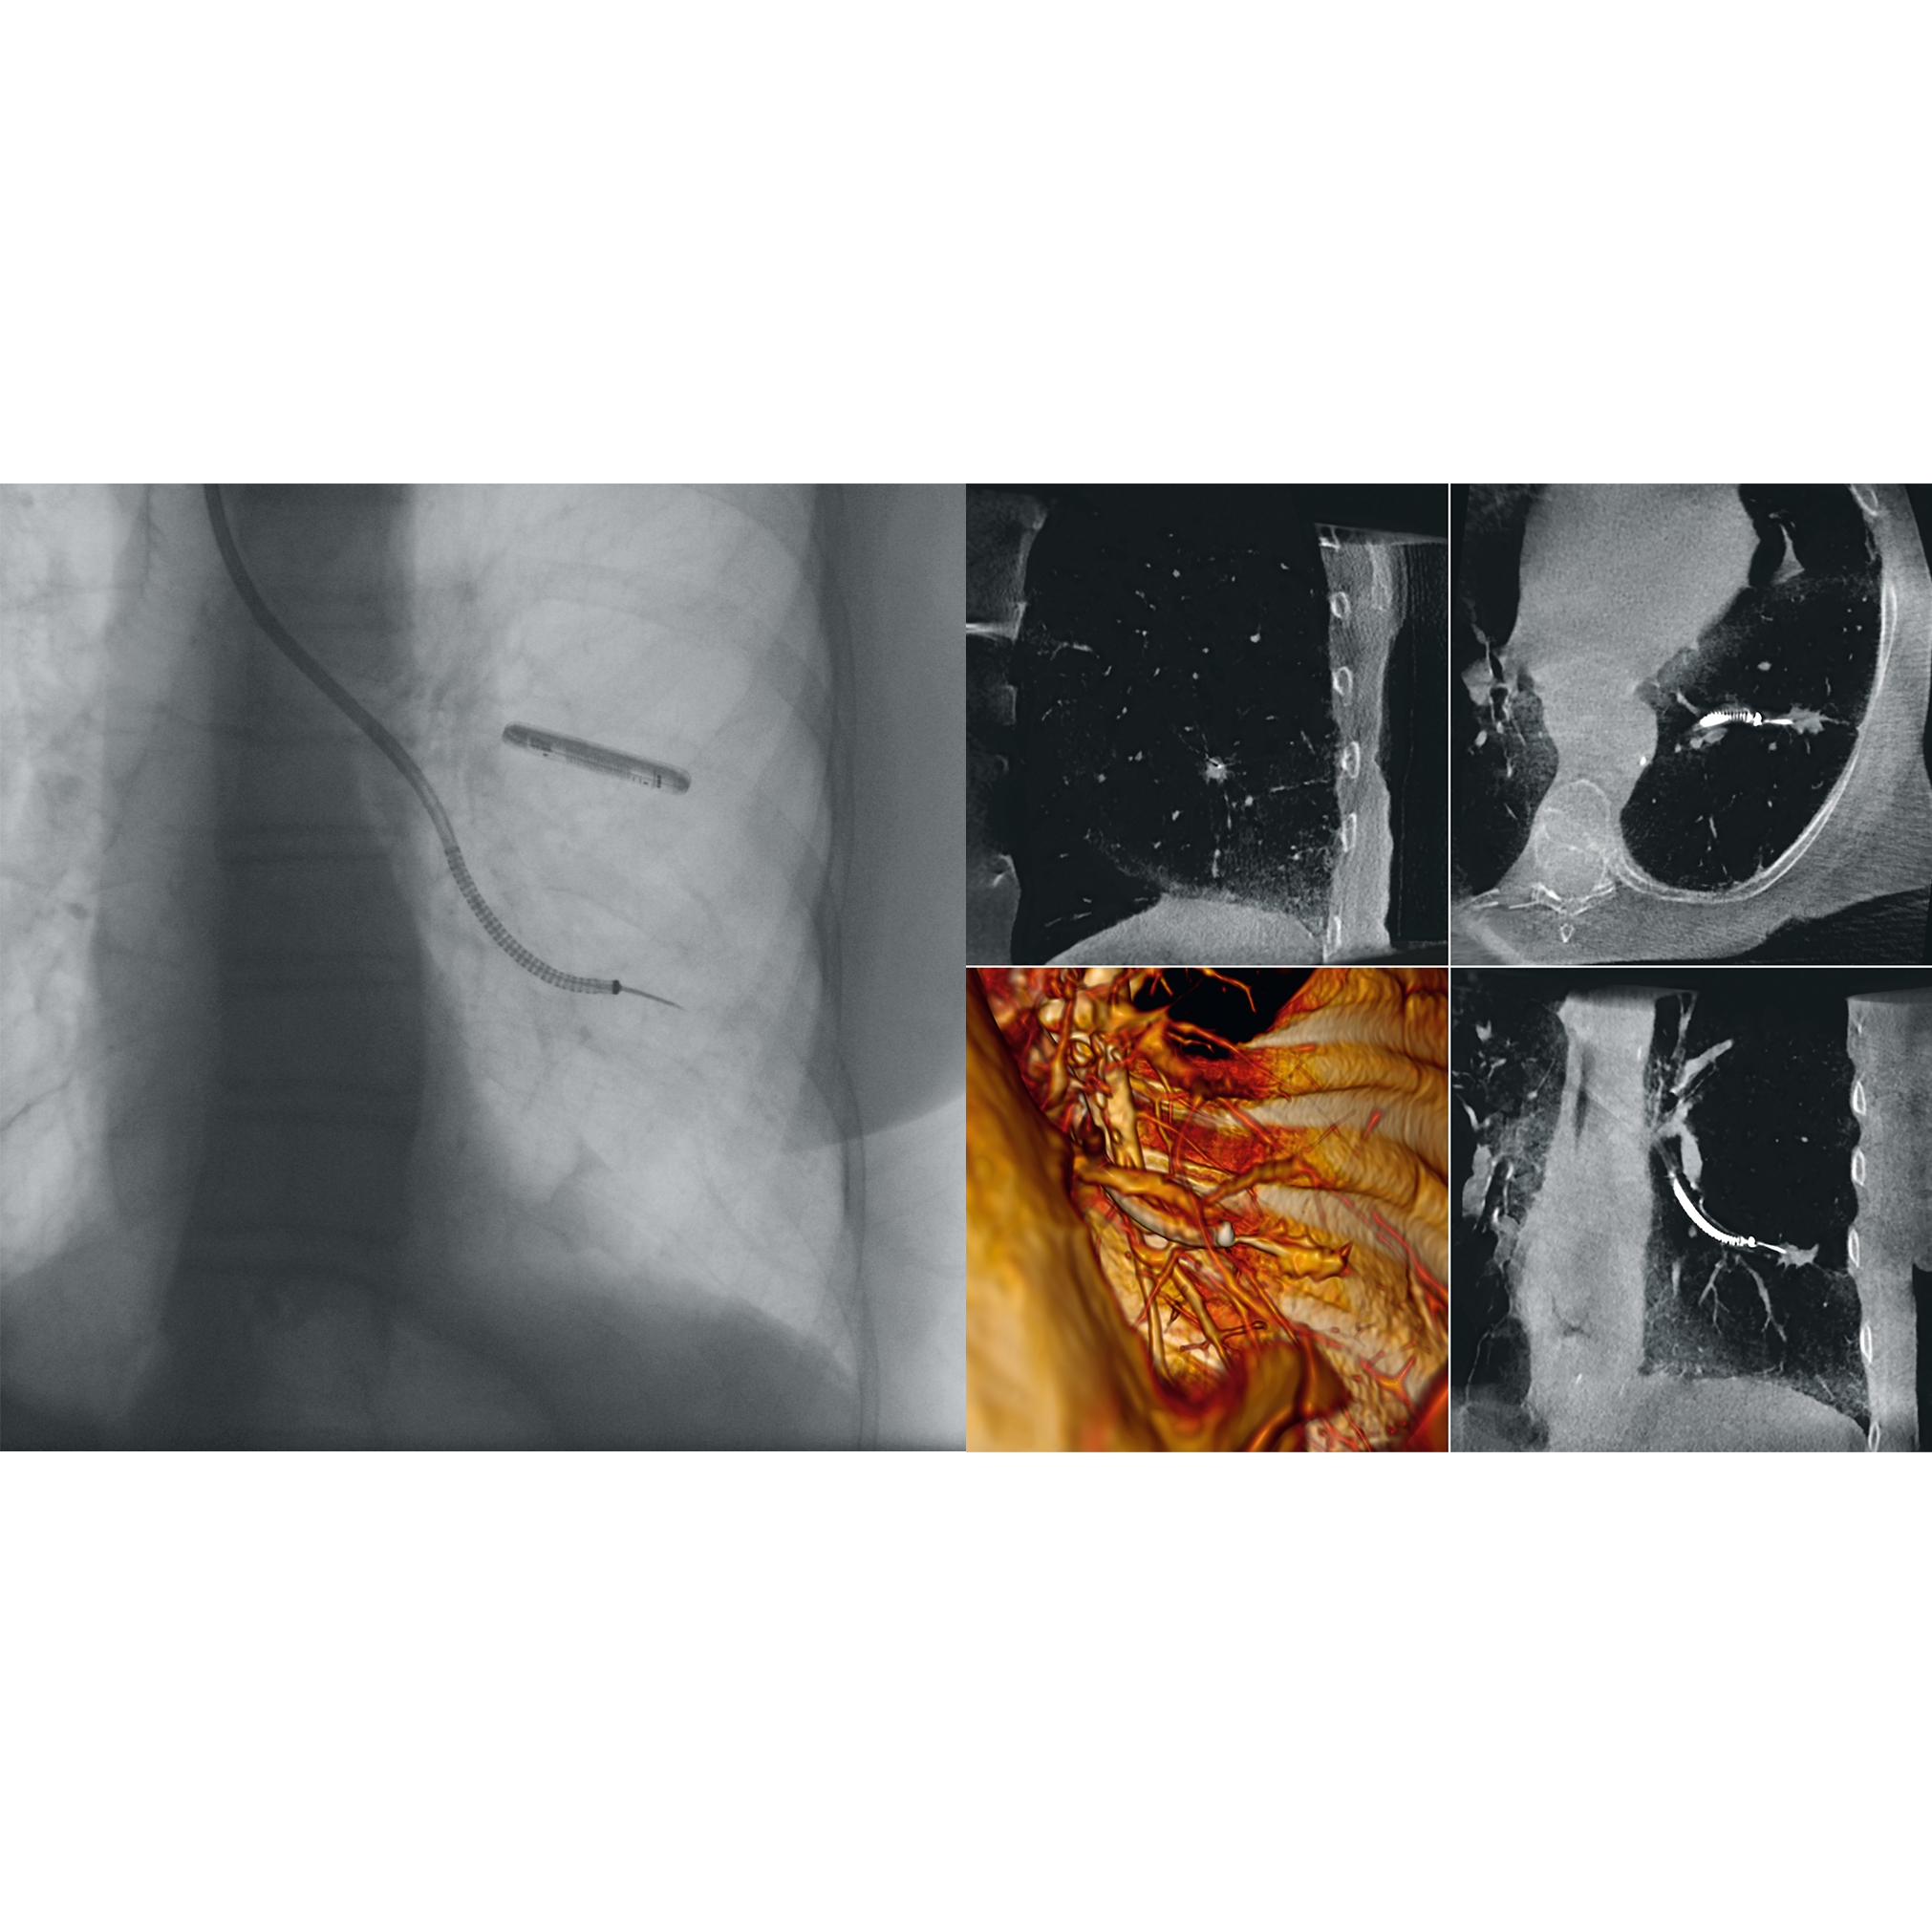

The best clinical images of the Ziehm Vision RFD 3D

3D Image fusion with Therenva EndoNaut

Intraoperative navigation system with image fusion to optimize endovascular procedures

Enhanced Vessel Visualisation (EVV)

Automated vessel detection during vascular interventions

SmartVascular Workflow

A special workflow for complex vascular procedures.